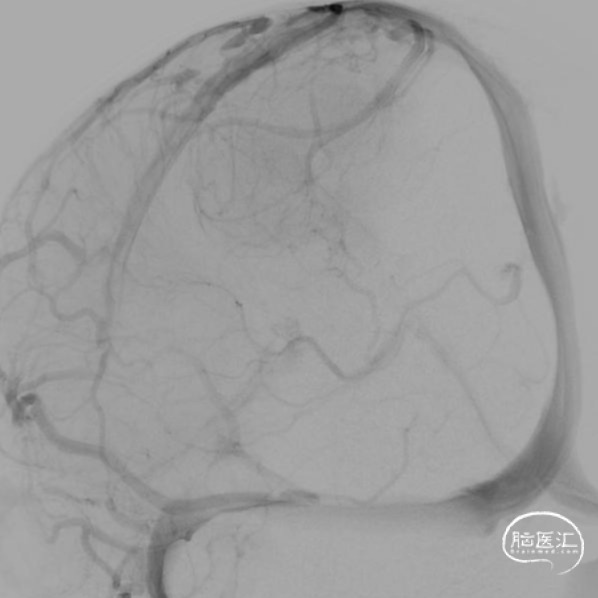

本例患儿肿瘤位于双侧额顶叶,大脑镰旁,增强扫描呈明显环形强化,提示肿瘤血运丰富。患儿年龄小,体重低,相对血容量少,如何控制术中出血是手术成功的关键。而术后肢体瘫痪或瘫痪加重是手术的主要并发症,中央沟静脉损伤、胼周动脉损伤、中央沟局部皮层损伤、癫痫、血肿以及脑水肿加重是其常见原因。术前脑血管造影有助于判断肿瘤与周围血管、组织的位置关系,明确上失状窦有无闭塞,对手术的切口设计有重要的参考价值及避免术中损伤不易发现的血管及组织。

本例患者术前脑血管造影提示瘤体主要由双侧大脑前动脉终末分支供血,造影静脉期瘤体显影明显,因此我们选择先采用神经介入技术超选部分主要供瘤动脉予弹簧圈栓塞,减少瘤体的供血。之后再行开颅探查双侧额顶叶占位性病变切除术。